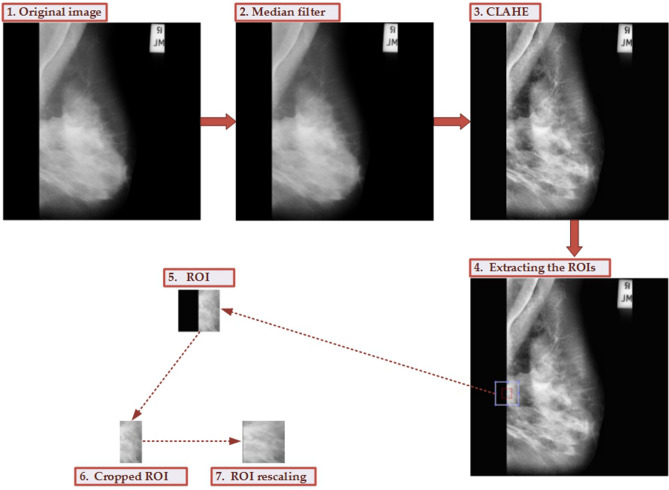

The original images from the MIAS dataset have strong noise. In order to remove the noise and improve image quality, the data preprocessing is essential before conducting model learning. The flowchart for the data preprocessing is given in Fig. 4. The median filter is employed to remove the noise, contrast limited adaptive histogram equalization (CLAHE)20 is used to perform image enhancement. After extracting the ROIs, the non-breast area is removed and is rescaled to 120 × 120 pixels. We provide the corresponding MATLAB scripts for this data preprocessing, and the source codes are available at https://github.com/yxchspring/MIAS_Preprocess.

Figure 4.

The whole process for data preprocessing and ROI extraction. The noise from the original image (1) is removed using the median filter (2). Then the image enhancement is performed using CLAHE (3). Extracting the ROIs (4) is carried out to obtain the ROI marked using a light blue box (the red box denotes the originally labeled area). And the black part of ROI (5) is removed to obtain the cropped ROI (6). Finally, the ROI rescaling is carried out to achieve the final ROI (7).